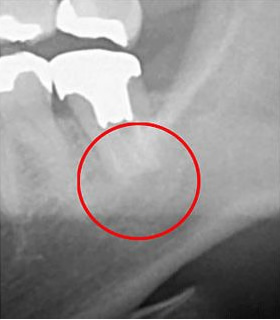

歯の内部にある根管は、肉眼では確認できません。その形状を把握するには、X線による検査が必要です。一般的には「レントゲン」が使用されますが、当院では「CT」を用いて詳細な検査を行っています。

レントゲンは2次元での撮影しかできませんが、CTはお口の周囲を回転しながら撮影し、立体的かつ鮮明な画像を提供します。これにより、より正確な診断が可能になります。

以下の画像は、同じ患部をCTとレントゲンで撮影したものです。

左側がCTで、右側がレントゲンの画像です。赤丸で示した部分には黒い影が現れています。これは炎症が起こっている箇所ですが、レントゲンではその影が確認できません。

つまり、レントゲンのみで診断すると、この炎症を見逃してしまうリスクが高くなります。気づかない間に炎症が進行し、最悪の場合抜歯が必要になることもあります。当院は、このような事態を防ぐため、CTによる診断を徹底しています。